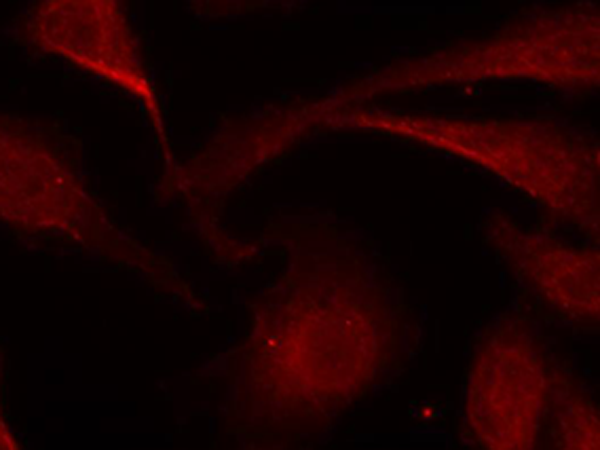

WB, IHC, IF

Positive control:

Hela cells

Recommended dilution:

100-200